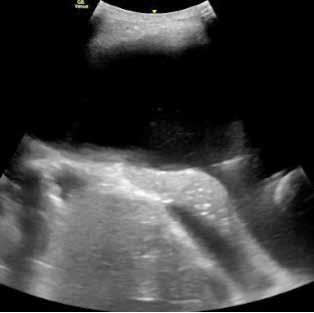

Con la sospecha de broncoconstricción durante el ejercicio y sin poder descartar una OLIE asociada, se solicitó un test BIE (según protocolo de nuestra Unidad de Neumología Pediátrica), con visualización simultánea de cuerdas vocales mediante laringoscopia contínua flexible, realizada por ORL infantil. La madre y la paciente, firmaron el consentimiento informado.

Previo al inicio de la prueba se comprobaron las constantes, saturación de oxígeno basal mediante pulsioximetría (SpO2), frecuencia cardiaca basal (FC) y tensión arterial basal (TA). Se realizó una espirometría basal forzada con medición del FEV1 (Figura 1) previo y se calculó la FC diana que debía alcanzar y mantener la paciente durante la prueba (85% de la FC máxima mediante la fórmula [220 - edad]).

Se administró lidocaína tópica en spray, previa a la introducción de fibroscopio flexible a través de la nariz, con fijación a un casco, y conectado a una pantalla para poder visualizar la laringe durante toda la prueba (Figura 2).

Se colocó una monitorización continúa, de frecuencia cardiaca y electrocardiograma con 12 derivaciones. Se realizó un test incremental en un solo escalón, mediante carrera libre en tapiz rodante (velocidad 6-8 km/h y pendiente 15%). Tras alcanzar la FC diana, se mantuvo el esfuerzo durante 6-10 minutos. A los 4 minutos de carrera, la paciente solicitó parar la prueba por disnea y opresión torácica (síntomas similares a los experimentados en la práctica deportiva). No se objetivó obstrucción laríngea durante la prueba, ni al finalizarla.

Figura 2. Imagen de la laringoscopia continua flexible, durante la prueba.